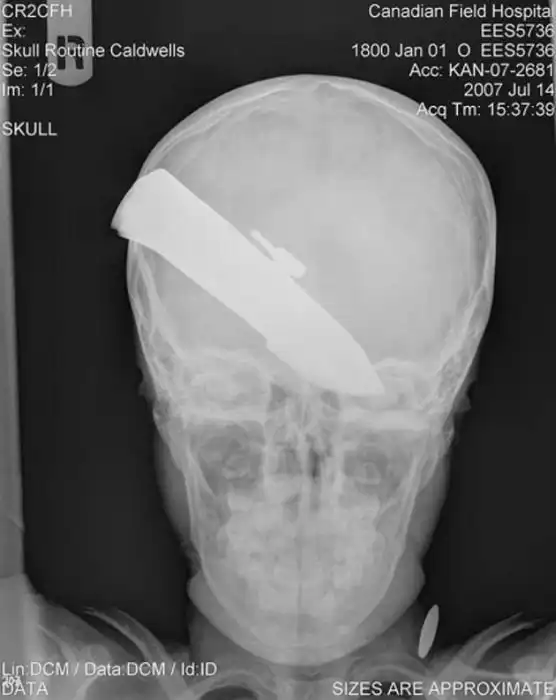

Порой даже не верится, с какими странными и необычными повреждениями в травматологию могут поступить пострадавшие. Всю эпичность профессии врачей травматологии могут с легкостью подтвердить рентгеновские снимки.